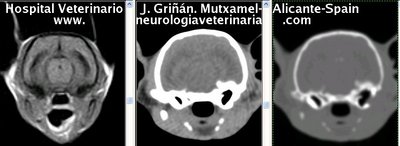

Se muestran cortes transversales de Resonancia Magnética (imagen a la izqda del lector), TC contrastado para tejidos blandos (imagen del centro) y TC contrastado para tejidos duros (imagen de la derecha del lector).

Nótese como la Resonancia supera al TC en el contraste de tejidos blandos (encéfalo y médula espinal) y en el de líquidos (ojo y líquido cefalorraquídeo), mientras que el TC supera a la resonancia en el contraste de tejidos duros (hueso) y aire (senos, cavidad nasal y bullas)

Cortes a nivel de los bulbos olfatorios